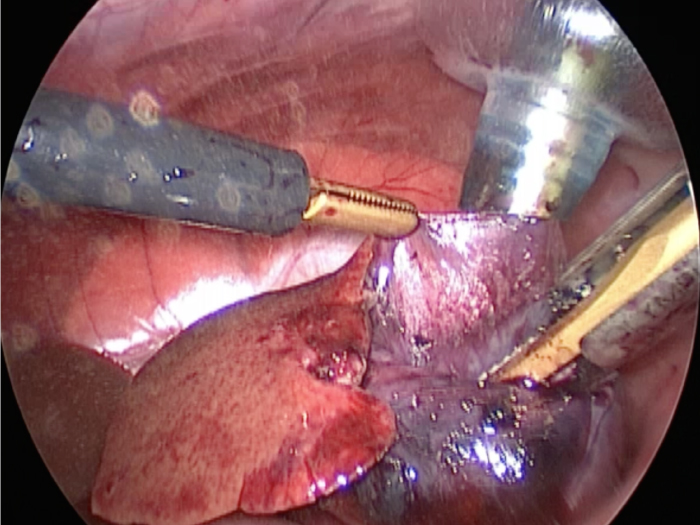

体の外に出すためお腹の中で袋に入れていきます。

このときに胆嚢と一緒にクリップやガーゼも回収します。

そしてお腹の中をきれいにしていきます。

最後にお腹の中をきれいに洗浄していきます。

回収袋にいれて体外に摘出していきます。

お腹の中を洗浄して終了となります。